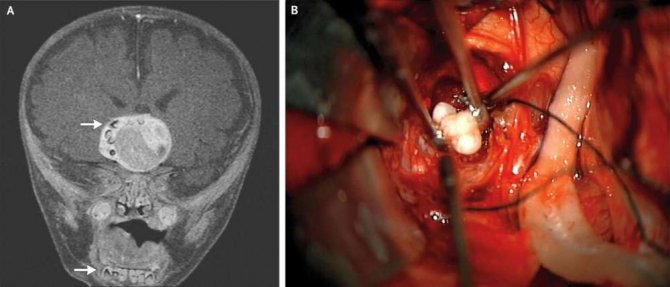

2014 yılında yaşanan vakada, Maryland Üniversitesi ve Johns Hopkins Çocuk Merkezi’nden nörocerrahlar, 4 aylık bir bebeği MRI beyin taramasından geçirdi.

Tarama işlemleri sonucunda çocuğun beyninde ceviz büyüklüğünde bir tümör keşfetti. Tümörün sağ tarafında ise çok sayıda küçük çıkıntı göze çarpıyordu. Bebeği hızla ameliyata alan cerrahlar tümörü aldı. Büyüyen kısmın craniopharyngioma adı verilen, embriyotik dokunun dönüşümüyle ortaya çıkan bir beyin tümörü olduğu ortaya çıktı. Genelde beynin hormon salgılama merkezine yakın olan bu yapılar, vakaların çok büyük bir kısmında salih tümörler oluyor (yani kansere dönmeyen ve yayılmayan çeşit) ancak hormonal merkeze yaptıkları baskı nedeniyle sorun yaratabiliyorlar.

Ancak vaka ile ilgili ilginçlikler bununla sınırlı kalmadı. Cerrahlar, tümörde birkaç tane tamamen gelişmiş diş buldular. Teratoma olarak bilinen bu yapılar, genelde farklı doku türleri bulundurabiliyorlar. Bu dokular saç, kas, kemik gibi farklı türlerden olabiliyor. Yine de doktorlar neden bu tümör üzerinde diş oluştuğunu bilmiyor.

Ancak vaka ile ilgili ilginçlikler bununla sınırlı kalmadı. Cerrahlar, tümörde birkaç tane tamamen gelişmiş diş buldular. Teratoma olarak bilinen bu yapılar, genelde farklı doku türleri bulundurabiliyorlar. Bu dokular saç, kas, kemik gibi farklı türlerden olabiliyor. Yine de doktorlar neden bu tümör üzerinde diş oluştuğunu bilmiyor.

Tümör alındıktan sonraki aylarda bebek hızlı bir şekilde iyileşti ancak tedavi edilebilir hormonal sorunlar yaşamaya devam etti. Bu nedenle de bebeğe tiroit ve adrenal hormon takviye tedavisi uygulandı. Alınan doku bir patologa gönderildi ve doku örnekleri, daha sonraki incelemeler için saklandı.